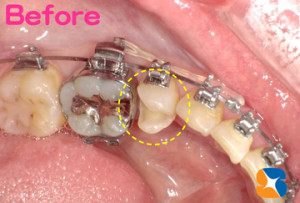

矯正中 詰め物とれた きちんと詰め直す

コラム「矯正中 詰め物とれた きちんと詰め直す」の画像